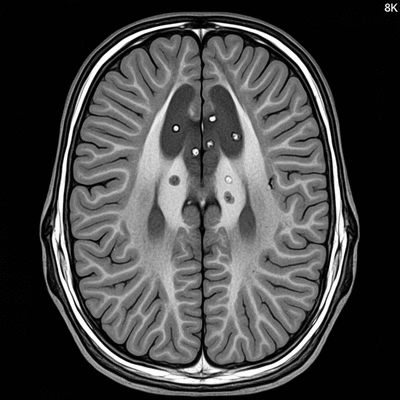

Role of MRI in MS Diagnosis: What Images Reveal

Detailed MRI scan of the human brain with highlighted lesions, indicating Multiple Sclerosis

Understanding MS Lesions: Diagnostic Implications

MS lesions can vary in appearance and location. Understanding these lesions is essential, as they provide key insights into the progression of the disease and your treatment options.